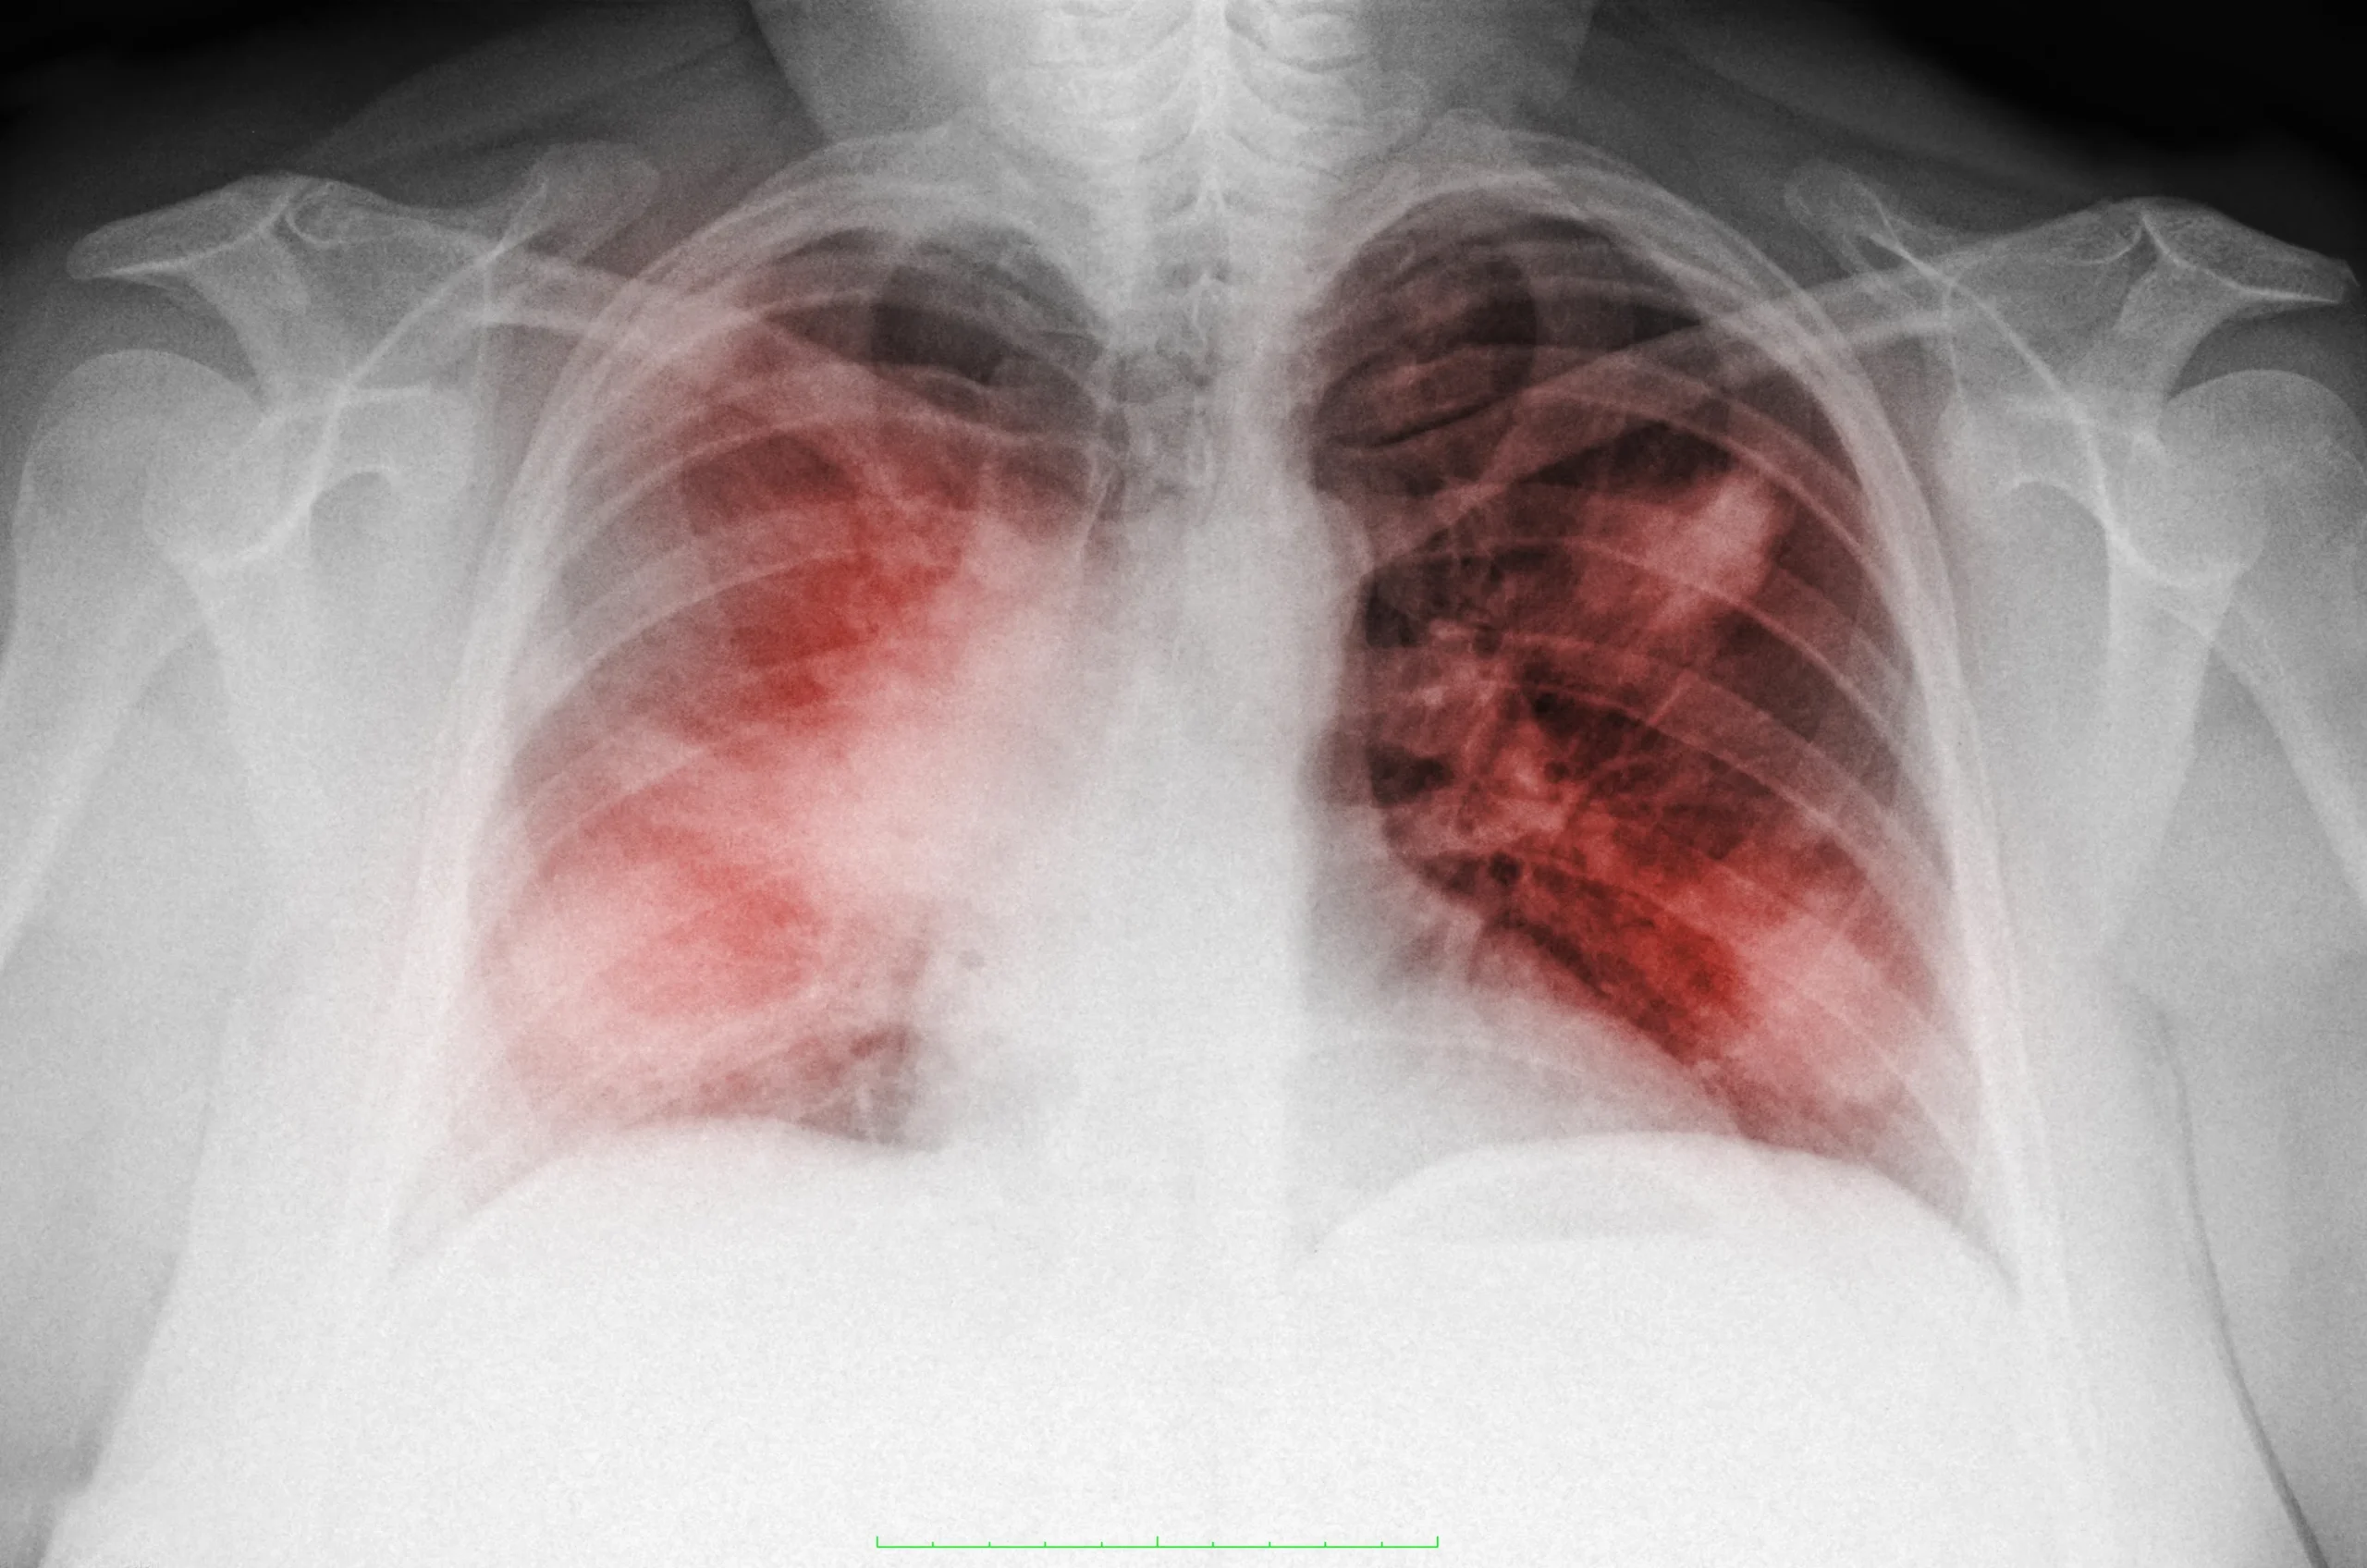

- Рентгенография грудной клетки: Позволяет визуализировать состояние легких и выявить наличие жидкости или воспалительных изменений.